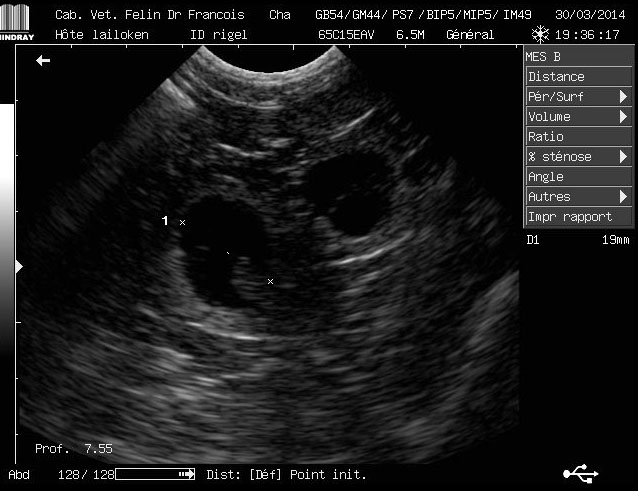

| échographie 3 semaines de gestation | |